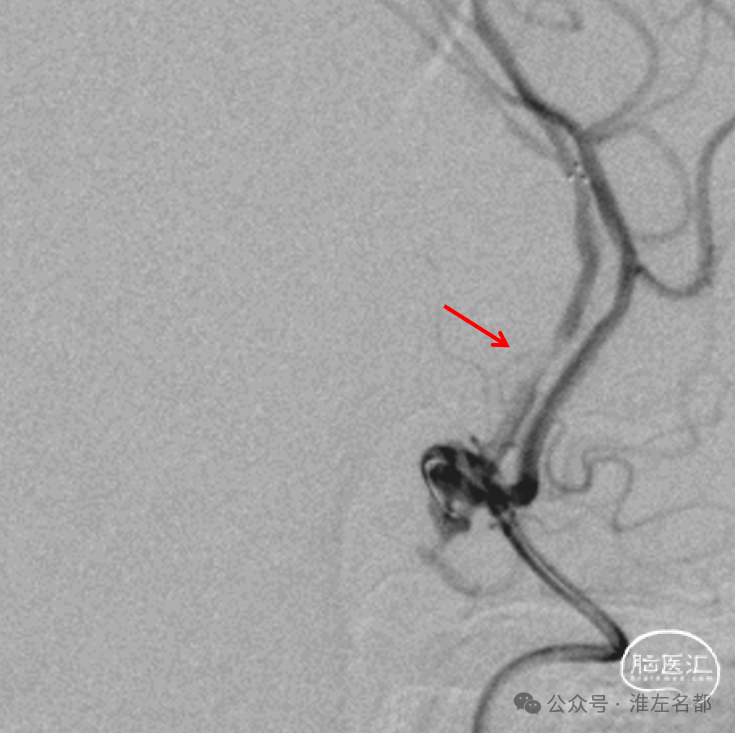

经微导管释放取栓支架(S AB 4*20mm)后造影,前向血流恢复,局部狭窄(红箭)。

回收取栓支架后造影:闭塞再通,右侧A2局部轻微狭窄,但A3-4交界处可见造影剂渗出,提示出血。

予以降压等处理,约5分钟后造影提示出血已经停止。